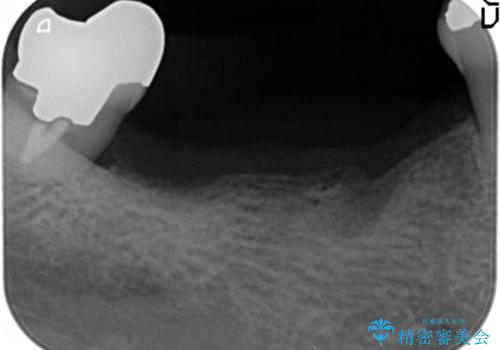

- 上の奥歯がないまま長年過ごしていたら前歯もぐらぐらしてきてしまったことを主訴に来院された患者様です。

奥歯の咬み合わせがないことにより前歯に負担がかかり動揺が出ていました。

精査したところ右下の奥歯も歯周病により保存不可能な状態でした。